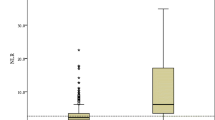

A total of 213 patients were enrolled in the final analysis, with 81 severe COVID-19 patients. Among the included patients, 94 (44.1%) patients were female; the median age was 47 years (33, 59 years); fever was the most common symptom before admission, and diabetes was the most common comorbidity. Age, body mass index, mean arterial pressure, heart rate, respiratory rate, neutrophil count, NLR, PLR, aspartate aminotransferase and alanine aminotransferase were higher in the severe COVID-19 group than in the non-severe group, and pulse oxygen saturation and lymphocyte count were lower in the severe COVID-19 group. Severe COVID-19 patients were more likely to have fever, sputum production, fatigue, dyspnea, diabetes, hypertension and chronic pulmonary disease (see Table 1).

For all patients, the median NLR was 3.28 (2.22, 5.80), with 2.88 (2.07, 4.16) in the non-severe group and 5.41 (2.90, 9.87) in the severe COVID-19 group. Variables found to be statistically significant (P <0.05) in univariate analysis were included in the multivariate logistic regression analysis to identify the independent risk factors for severe COVID-19. After adjustment for confounders, the NLR was found to be an independent risk factor for severe COVID-19 (OR, 1.155, 95% CI, 1.043–1.279, P = 0.006).

The patients were divided into 4 groups according to the interquartile NLR, they were less than 2.22, 2.22–3.28, 3.28–5.80 and greater than 5.80. The occurrence rates of severe COVID-19 in each quartile group were calculated, and were 22.6%, 24.1%, 39.6% and 66% in the first quartile, second quartile, third quartile and fourth quartile, respectively. Based on the statistical analysis result of the Cochran-Armitage test for trend, there was a linear relationship between the NLR level and the occurrence rate of severe COVID-19, which visibly increased with the increase in NLR (P <0.001). The result is described in Fig. 1.